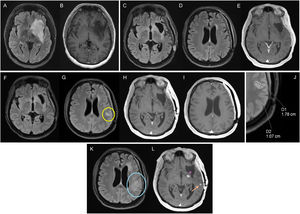

Figure 3.76-year-old woman diagnosed with right parietal glioblastoma demonstrated on MRI with FLAIR sequences, post-contrast T1 and CBV mapping in DSC perfusion (A–C). Complete resection of the contrast-enhancing component in the 24-h postoperative MRI (D). In the post-radiotherapy MRI (E,F), corresponding to the baseline MRI, there is a parietal nodular area of contrast enhancement (asterisk) without significant increase in volume in the CBV mapping of the DSC perfusion study (F). In the subsequent scans, six weeks (G) and 12 weeks post-concomitant RT and CT (H, I), a reduction in the size of the area of enhancement can be seen, without an increase in volume (I), findings related to pseudoprogression.

CBV: cerebral blood volume; DSC: dynamic magnetic susceptibility testing; MRI: magnetic resonance imaging.

82-year-old man diagnosed with glioblastoma in the right superior frontal gyrus. Diagnostic MRI with FLAIR (A) and post-contrast T1 (B) sequences, showing a small anterior paramedian frontal focal enhancement (arrowhead). In the postoperative MRI (C–E) pericavity enhancement can be seen without alteration in diffusion (D), corresponding to residual tumour (arrows). A pre-radiotherapy MRI was performed, showing an increase in the size of the contrast-enhancement component, now measurable (F). In the post-radiotherapy MRI corresponding to the baseline MRI, the contrast-enhancement component (G) has disappeared. In the 1st follow-up MRI three months post-concomitant RT and CT (H), a new measurable lesion is evident, conclusive of disease progression.

MRI: magnetic resonance imaging.

GB: If DP is suspected on MRI within 12 weeks after RT, conMRI should be performed, as the incidence of PsP is high in this period.32 This conMRI should be performed within four to eight weeks after the suspect MRI, where the changes should be referred to as preliminary progression (PreP). If DP is confirmed on conMRI, the PreP MRI will be the MRI diagnostic of DP (Fig. 5). However, if DP occurs outside the irradiation field, or there is confirmation by pathology, conMRI is not required. Beyond 12 weeks, conMRI would not be necessary (Fig. 4).

One thing to be considered is performing an MRI one to two weeks before starting RT (pre-RT MRI). This is necessary in most clinical trials and also recommended in international guidelines for its prognostic role and help in delimiting the irradiation area.49 Several studies have shown GB tumour growth between surgery and starting RT in around 40% of cases50,51 (Fig. 4), being more likely in patients with partial resections. A pre-RT MRI could therefore also reduce PsP diagnoses, particularly in cases with a delay in the start of treatment.

DP on bMRI. In RANO-2.0, bMRI is the initial test for monitoring the disease's progress, but they do not specify what course of action to take if there is suspected DP on this scan. If the bMRI corresponds to an MRI prior to the start of treatment (pre-Trt MRI) with suspected DP, as there is no risk of PsP, the DP is assumed to be real. If it is a post-RT MRI, if the changes are outside the irradiation area they also suggest actual DP. However, if the changes are within the irradiation area, the conMRI should be performed (Fig. 5). The dilemma of PsP therefore has to be kept in mind both in the bMRI and subsequent MRI scans in the first 12 weeks after RT. Finally, if the post-RT MRI does not show any suspicion of DP, the next check-up would be in three months, by which time the PsP dilemma has disappeared for GB (Fig. 4). It should be noted that in IDHm, PsP may exist beyond 12 weeks after RT,59 so an MRI after this period will depend on clinical and radiological criteria.